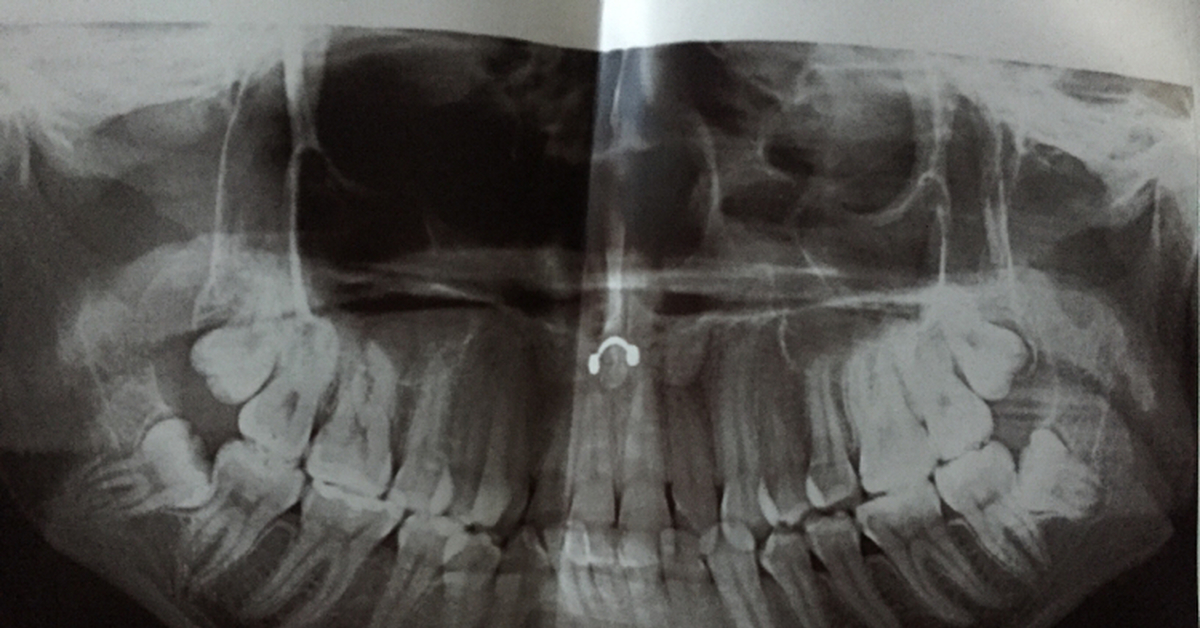

Рентгенография небного шва: Медицинские исследования и диагностика

Раздел: Фотопутеводитель